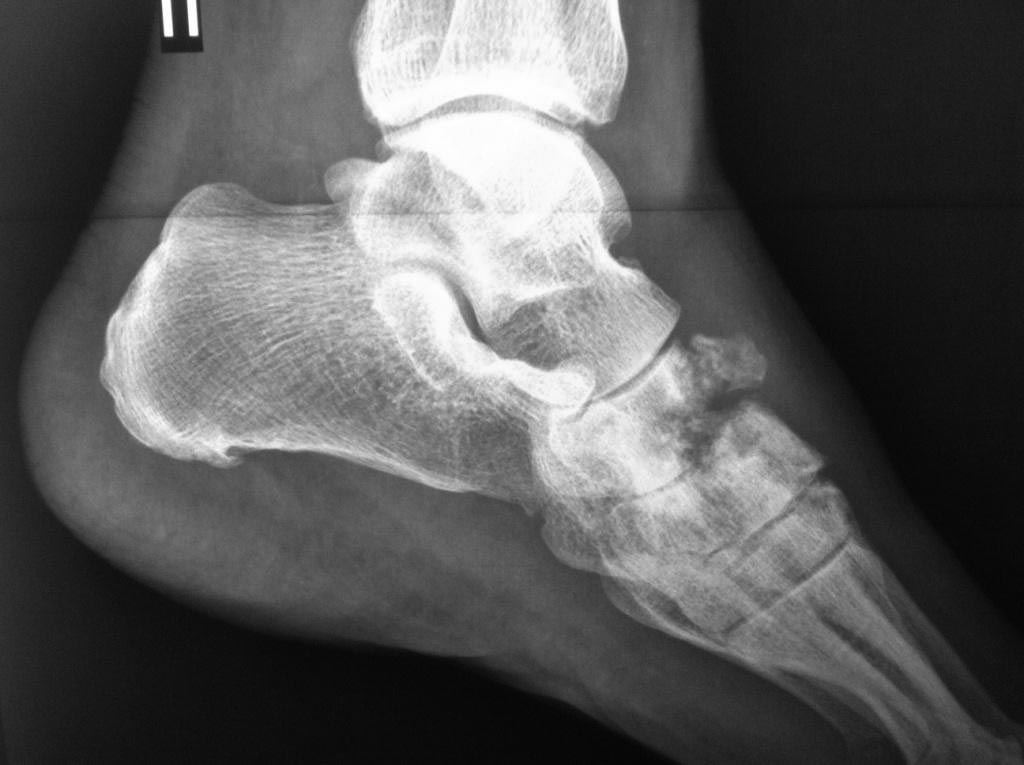

Асептический некроз костей среднего отдела стоп.

Доброго времени суток. Обратился пациент, 62 года, бытовые и трудовые условия в данное время не отягощены и не были никогда тяжелыми, без вредных привычек,

со слов оперативных вмешательств не было, курсов гормональной терапии не получал, периодически принимает лекарственные препараты от арт. гипертензии. Без видимых причин около 1 года назад появились боли в стопах при ходьбе и нагрузке, в связи с чем обратился к ортопеду.

Лаб исследования: Ревмофактор, С-реакт. белок, АЦЦП, Мочевая кислота и др. в пределах возрастной нормы. Хотелось бы услышать мнения. Заранее благодарен.

Добрый день. Похоже на Charcot

И, забыл добавить, есть мнение, что ингибиторы АПФ, например эналаприл, эту саму артропатию Шарко могут вызывать.